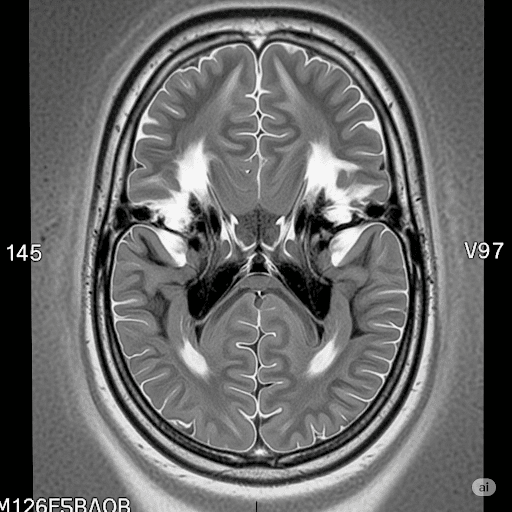

Magnetic Resonance Imaging (MRI)

An MRI is the “gold standard” for pediatric neuroimaging. It uses a powerful magnetic field and radio waves to create highly detailed, cross-sectional images of the brain’s soft tissues. It is the most effective tool to see the nature and extent of an injury. An MRI is the best way a brain scan show cerebral palsy-related damage with high precision. Because of its clarity, the MRI is the most valuable type of scan in a legal investigation asking can a brain scan show cerebral palsy?